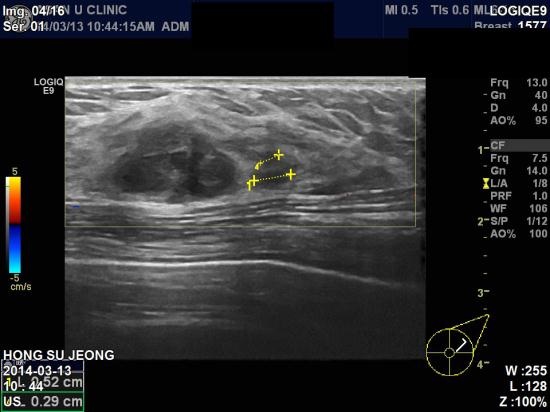

아산유외과 개원 후 78번째 유방암진단.

2014.3월에 실시한 건강검진(유방촬영)에서

좌측유방 결절소견으로 내원하신 45세 여자분이십니다.

본원에서 초음파 검사결과 좌측1시방향에 2cm 의 결절이 있었고

좌측유방에 림프절 비대소견있어 조직검사과 세포검사시행결과

침윤성유관암으로 진단되었습니다.

다행이 세포검사상 겨드랑이 림프절엔 전이소견이 없었으나

대학병원으로 전환하여 PET(양전자단층촬영)와,

유방 MRI 검사를 통해 치료계획을 세울예정이십니다.